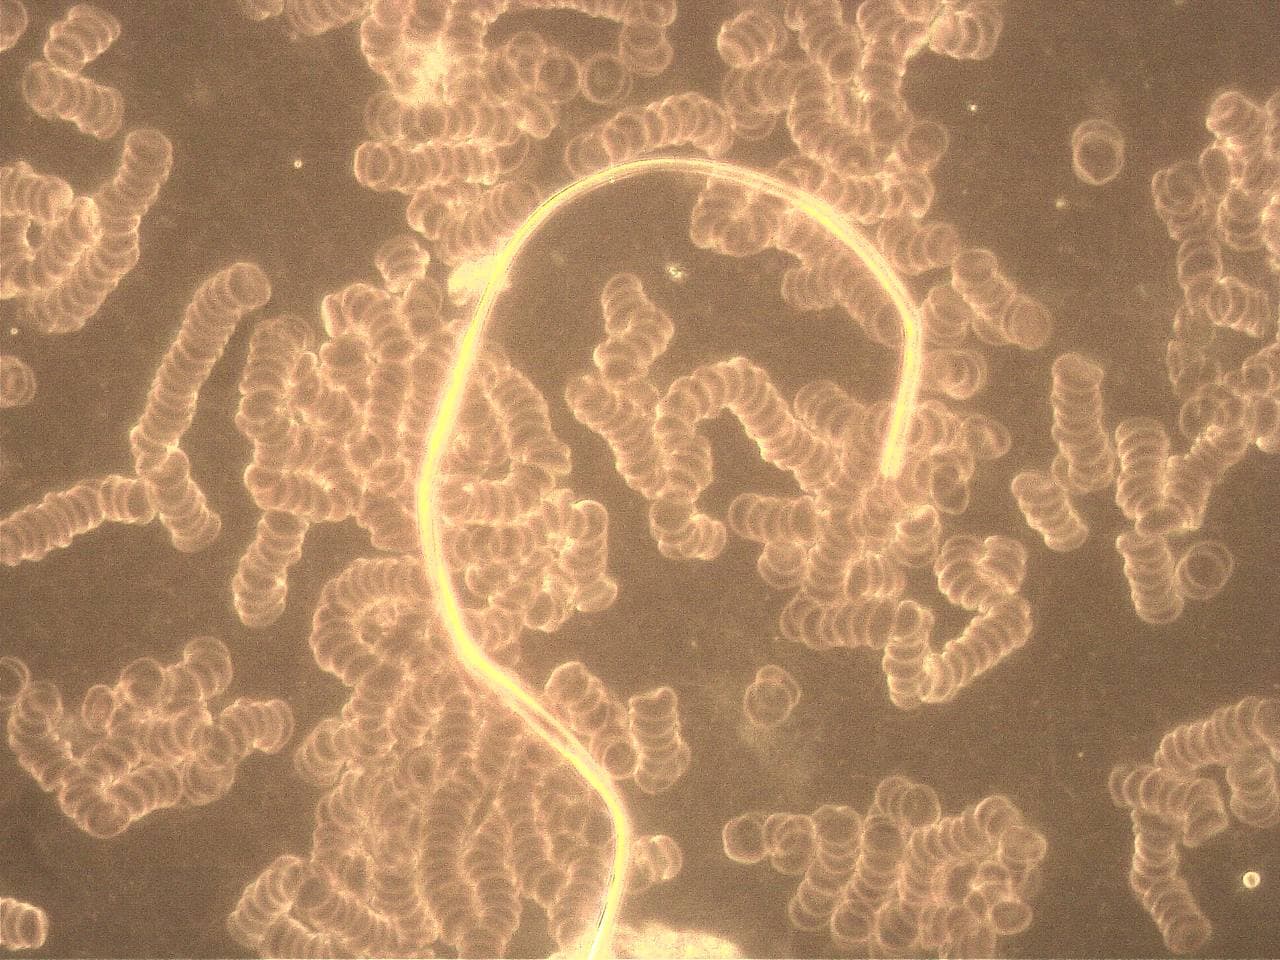

GENimpfschaden Blut nach GENimpfung Schweiz

Diese Dunkelfeld-Bilder wurden am 28.09.2021 vom Blut eines

18 jährigen Mannes aufgenommen, der 10 Tage zuvor die erste

Dosis mit Biontech/Pfizer bekommen hatte. Sie zeigen

Anomalien, die die Untersuchende (Name ist Kanalbetreiberin

bekannt) laut ihrer Aussage in ihrer langen Zeit der Praxis

noch nie zuvor gesehen hat. Auch derjenige, der die Bilder

direkt vom Bildschirm abfotografiert hat, ist pers. bekannt.

GENimpfschaden: Blut

Blutkiörperchen sind "gestapelt"

https://t.me/Impfschaden_Corona_Schweiz/28815

Liebe Mara, das Blutbild diesen 18jährigen ist wohl der

Blut kaputt nach GENimpfung 6.11.2021: Die roten

Blutkiörperchen sind "gestapelt" [19]

Blut kaputt nach GENimpfung 6.11.2021: Die roten

Blutkörperchen sind "gestapelt" [20]